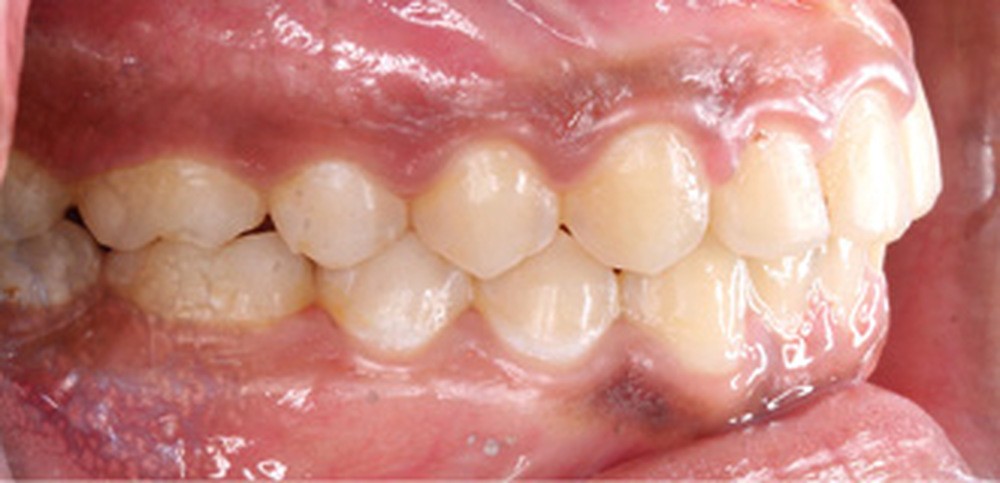

Examen clinique (fig. 1a-h)

L’examen clinique endo-buccal révèle une denture adulte jeune avec un inversé d’articulé antérieur de 13 à 23, des tatouages gingivaux ethniques et des taches de décalcifications, un parodonte sain mais un brossage insuffisant.

L’arcade maxillaire est en V et la voûte palatine profonde. L’arcade mandibulaire a une forme en U (non-concordance des formes d’arcade) et présente des malpositions des dents cuspidées. La médiane mandibulaire est décalée à gauche de 2 mm ; le recouvrement antérieur est de 2 mm ; les molaires sont en classe III avec un surplomb inversé.